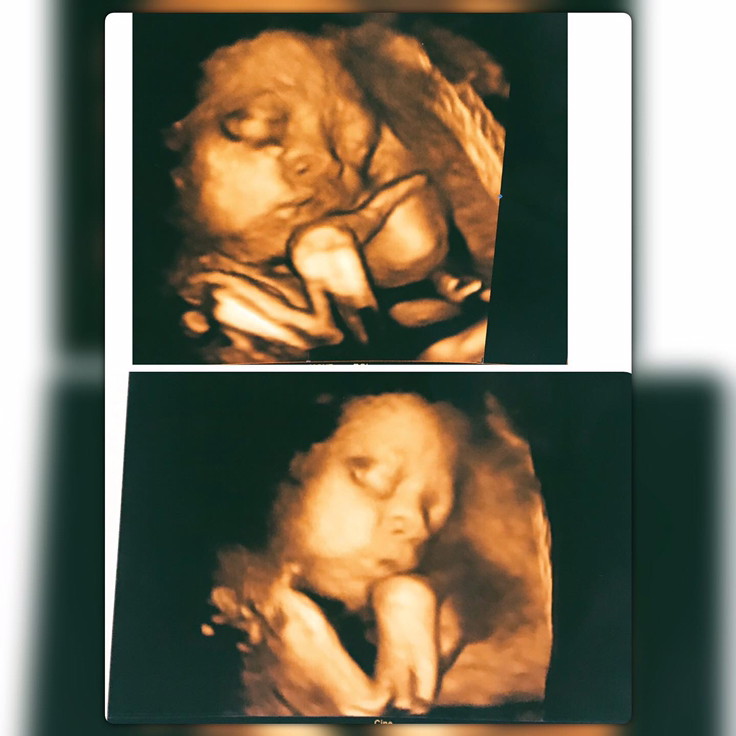

28w4d ค่ะ

32wค่ะ